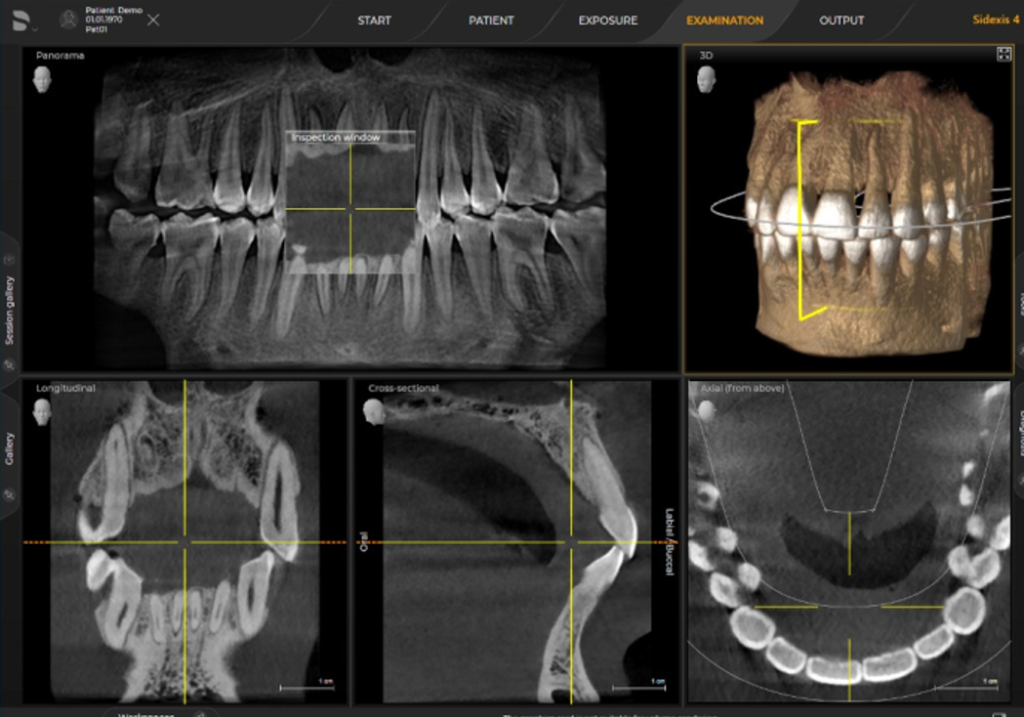

Дентальна комп’ютерна томографія (КТ) — це діагностична процедура в сучасній стоматології. Її результат дозволяє терапевту достовірно оцінити стан та анатомічні особливості кореневих каналів, локалізувати запальний процес. Ортопед може побачити точне розташування, будову СНЩС, імплантолог — оцінити параметри щелепної кістки, структуру, щільність та об’єм.

3D знімок — точний метод діагностики, лікар отримує повну інформацію про стан щелепно-лицьового апарату пацієнта, гайморових пазух. Отримані в результаті сканування знімки дають можливість стоматологу збільшувати, повертати і досліджувати під кутом області, що цікавлять, що неможливо при рентген-дослідженні. Також комп’ютерна томографія вимірює висоту, ширину кістки, визначає тип. Це потрібно, щоб підібрати розмір та тип імплантату при плануванні операції.

ORTHOPHOS SL 3D. Довершена рентгенівська система для будь якої практики.

ORTHOPHOS S 3D це прилад з всеохоплюючими можливостями. Починаючи з надчітких панорамних 2D знімків завдяки сучасному DCS сенсору і аж до максимальної гнучкості у виборі 3D обєму зйомки (11Х10, 8Х8, 5Х5). У коплексі з програмним забезпеченням SIDEXIS 4 відкриє нові можливості для Вашої практики.

Три розміри об'єму зйомки на вибір

Точність для вірної діагностики та ефективне використання часу

Поле огляду 8 см х 8 см (VOL1) дозволяє відобразити всю щелепу пацієнта на одному знімку, що спрощує діагностику та планування лікування. При ендодонтичному лікуванні достатньо меншого обєму 5смХ5,5см (VOL2). Таким чином ми не тільки зменшуємо дозу опромінення а й скорочуємо час на постановку діагнозу. В режимі HD (висока роздільна здатність, 500 знімків зо один оборот ) при VOL2 з розміром вокселя 100 мкм Ви отримаєте надчіткі знімки для ендодонтичного лікування. Обєм 11 см Х 10 см надасть Вам максимум потрібної інформації.